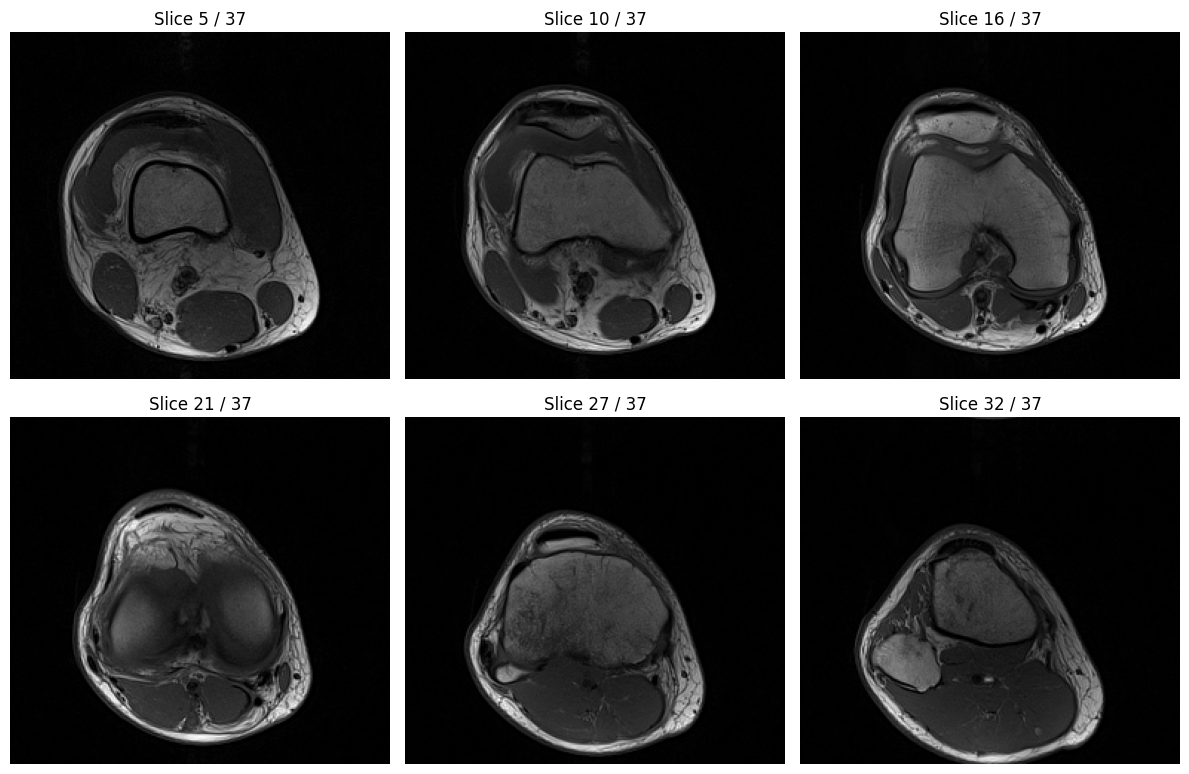

# Visual comparison

mid_idx = len(volume) // 2

fig, axs = plt.subplots(1, 2, figsize=(12, 6))

axs[0].imshow(volume[mid_idx], cmap='gray')

axs[0].set_title('Original Volume (Slice {})'.format(mid_idx))

axs[0].axis('off')

axs[1].imshow(nvimg_decoded_cpu[mid_idx], cmap='gray')

axs[1].set_title('nvImageCodec Decoded (Slice {})'.format(mid_idx))

axs[1].axis('off')

plt.tight_layout()

plt.show()

⏱️  pydicom decode time:     0.0675s (1.78 ms/file)

⏱️  nvImageCodec decode time: 0.0367s (0.96 ms/file)

🚀 Speedup: 1.84x faster

✓ All decoded slices match original